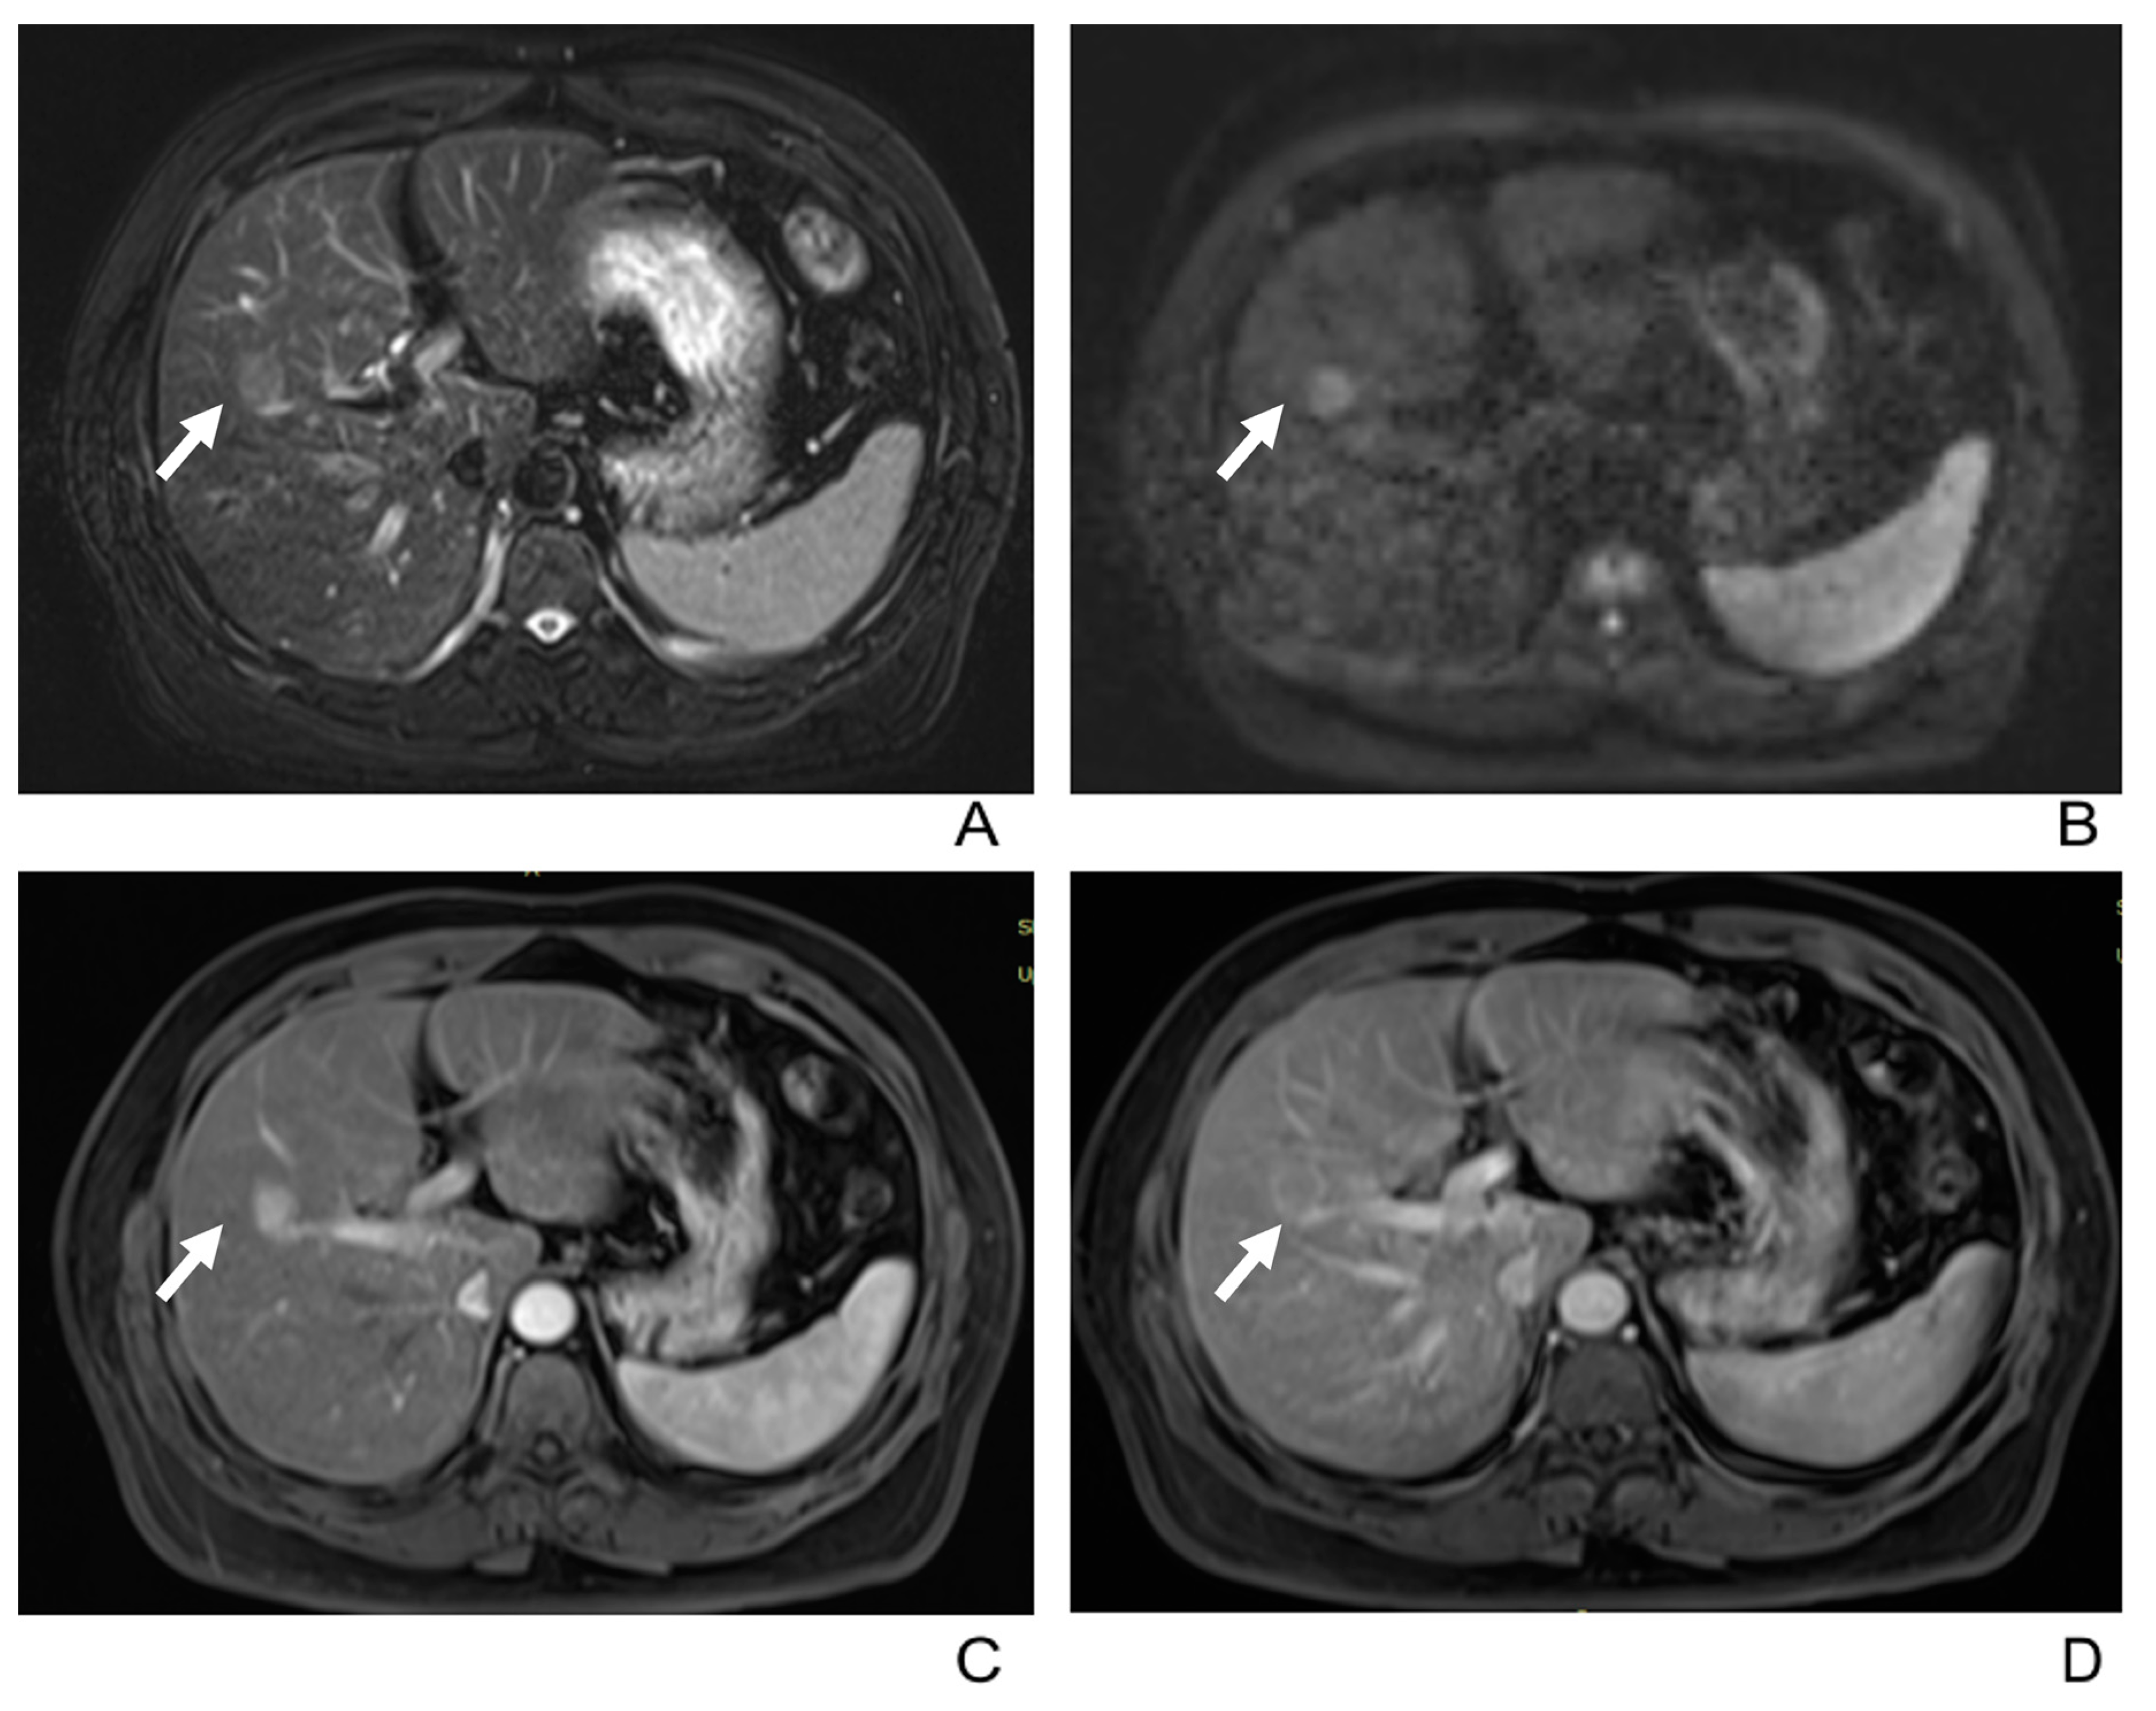

3.2. Imaging Manifestations

- Only two lesions showed a scar-like enhancement in the tumor in AP.

- Two tumors had associated satellite lesions.

- Four patients had portal vein tumor thrombosis (Figure 3).

- Three patients exhibited intrahepatic biliary dilation, and one patient had distal metastasis on the 12th rib (Figure 3).

- Furthermore, lymph node enlargement was found in 9 patients, and metastases were discovered pathologically in 11 patients. The median short-axial diameter of the lymph node was 2.1 cm (range, 0.7 cm to 2.9 cm). Only two lymph nodes had necrosis inside, while the others all showed homogeneous hypervascular enhancement.

- Two patients underwent the gadoxetic acid-enhanced MRI, and both tumors showed hypointense in the hepatobiliary phase.